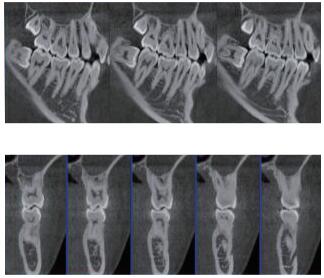

三維重建任意斷層

專有三維重建算法,可提供任意位置高清斷層影像。

多平面組合重建

可同時(shí)觀察軸向面、冠狀面和矢狀面圖像,方便臨床診斷。